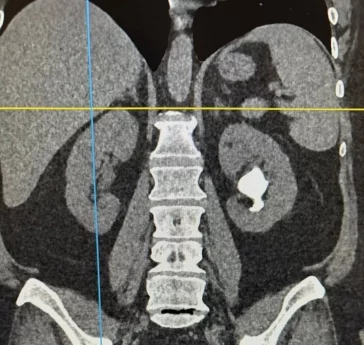

У жительницы Кузбасса был выявлен обширный коралловидный почечный камень. Раньше в таких случаях почку удаляли, однако кемеровским врачам удалось вывести образование и сохранить орган.

По словам врача-уролога Павла Сафронова, сложность вмешательства состояла в том, что коралловидный камень имеет ветвистую структуру. У пациентки он занимал всю полость почки, самый крупный сегмент образования достигал 6 см. Операция длилась около часа.